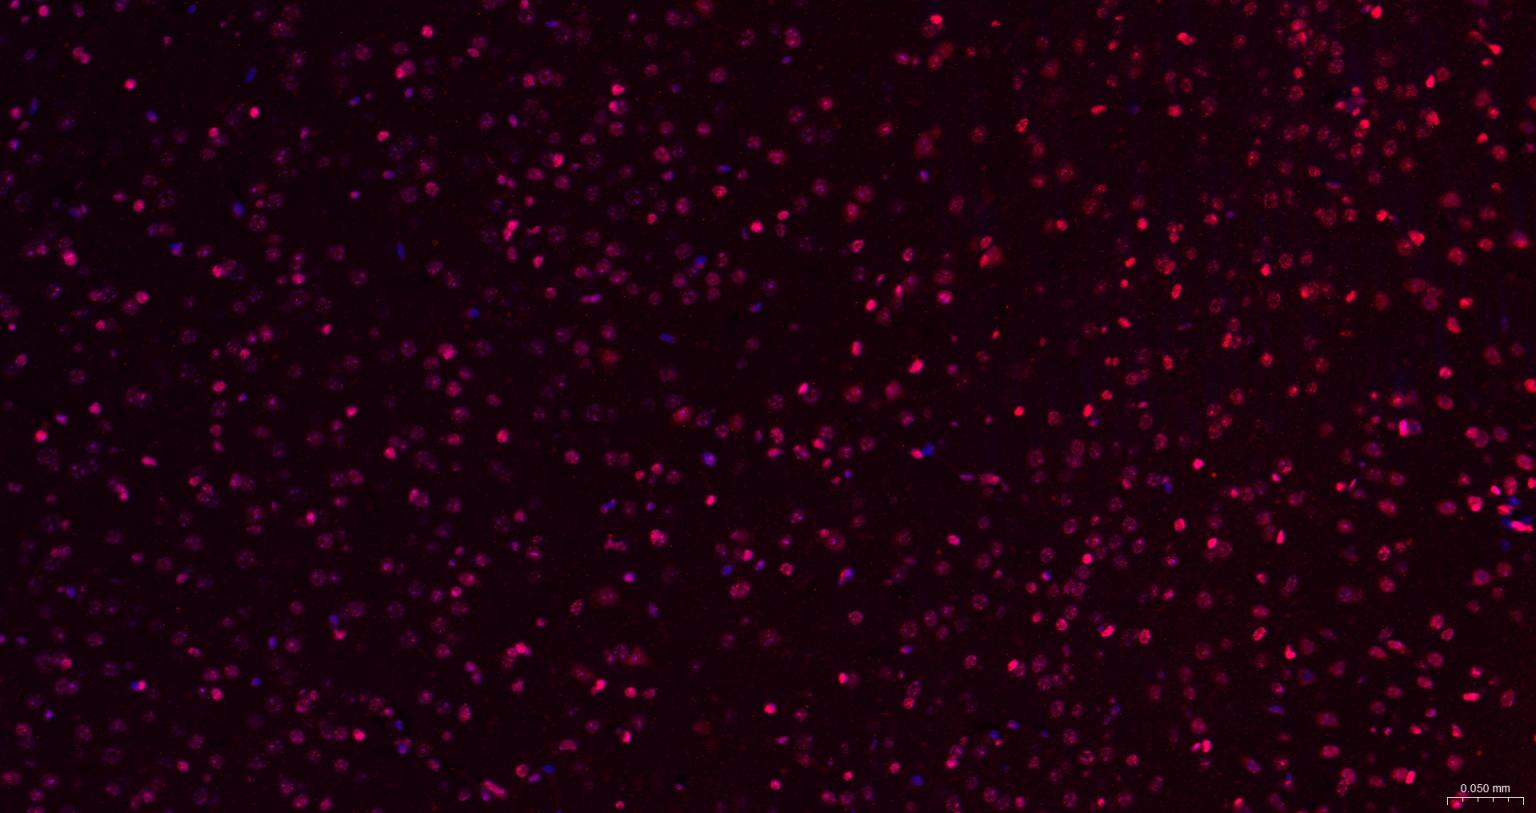

Paraformaldehyde-fixed, paraffin embedded Rat Cerebrum; Antigen retrieval by boiling in sodium citrate buffer (pH6.0) for 15 min; The section was incubated with CIDEC Polyclonal Antibody, Unconjugated (bs-6796R) at 1:200 overnight at 4°C. Followed by conjugated Goat Anti-Rabbit IgG antibody (Red, bs-0295G-BF594), DAPI (blue, C02-04002) was used to stain the cell nuclei.